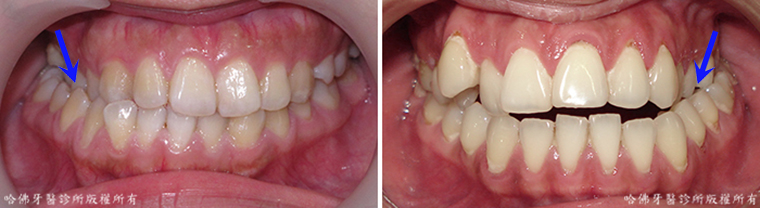

一些人對齒顎矯正治療療效有所誤解,認為它僅能排列不正常的齒列。其實,在恰當而計劃周全的齒顎矯正治療中,令「齒列正常排列」僅是治療最基本的能力。齒顎矯正治療除了能有效更正「排列不良的齒列」外,也能與透過對顎骨的生長刺激式抑制,改善顎骨缺陷引發的美觀不協調。此外,齒顎矯正治療也可與口腔外科醫師合作,利用正顎手術改善「發育異常的顎骨」。這種顎骨改善的手術也可明顯改良臉部外觀與微笑(圖14)。

(圖14)齒顎矯正治療可與口腔外科醫師合作,利用正顎手術改善「發育異常的顎骨」。左圖:治療前;右圖:治療後。